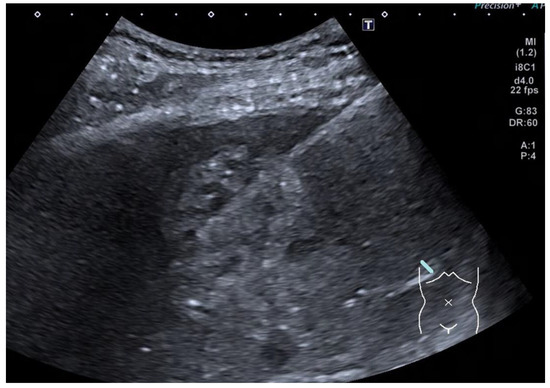

4.1. Seminomatous Germ Cell Tumour

| Seminomas | Homogenous and hypoechoic Well circumscribed Occasionally contain cystic components or calcifications |